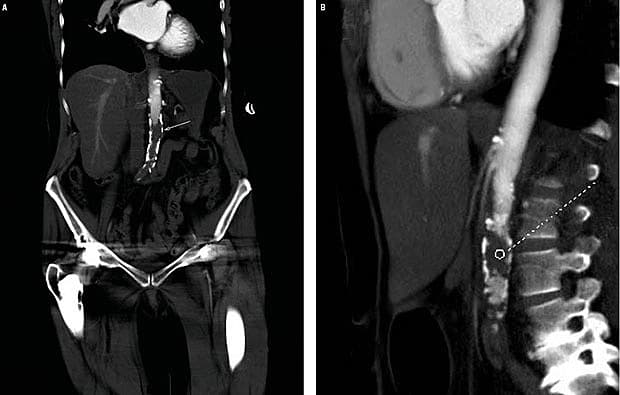

En 77-årig kvinde med kronisk obstruktiv lungesygdom, systemisk lupus erythematosus, kroniske lænderygsmerter og tidligere apopleksi blev indlagt via Falck pga. pludseligt opstået nedsat kraft og sensibilitet samt smerter i højre crus. Patienten havde claudicatio. Objektivt vurderet var hun vågen, klar og velorienteret ved ankomsten. Den højre underekstremitet var lidt bleg, kølig og pulsløs. Hun blev tiltagende dårlig med kraftig progrediering af forløbet over få timer, hvor begge ben blev fuldstændigt kølige, blåmarmorerede og paretiske. Der blev foretaget CT af abdomen på mistanke om aortaaneurisme, men skanningen viste tromboseret aorta abdominalis 2 cm distalt for afgangen af nyrearterierne. A. Trombe i aorta abdominalis i koronalt plan. B. Trombe i aorta abdominalis i sagittalt plan. Patienten blev overflyttet til en karkirurgisk afdeling og gik ad mortum kort tid efter.